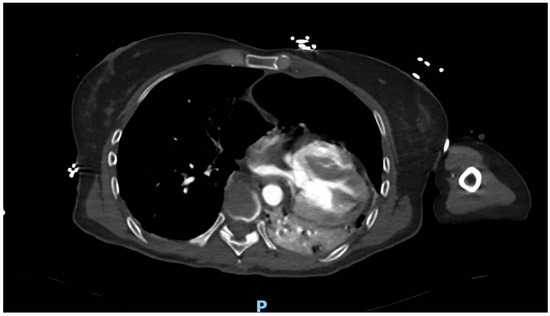

The 3D reconstruction enabled a better visualization of the pericardial damage and the displacement of the heart within the thoracic cavity, which was significantly shifted to the left. (Figure 2).

Figure 2. Three-dimensional reconstruction highlights abnormal position of the heart.